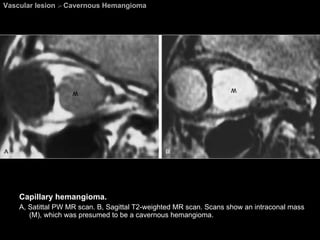

Vascular lesion  >  Cavernous Hemangioma Capillary hemangioma.  A, Serial axial CT scan. B, Reformatted coronal CT scans. A and B show a well-defined intraconal markedly enhancing hemangioma (H ).

Vascular lesion  >  Cavernous Hemangioma Capillary hemangioma.  A, Satittal PW MR scan. B, Sagittal T2-weighted MR scan. Scans show an intraconal mass (M), which was presumed to be a cavernous hemangioma.